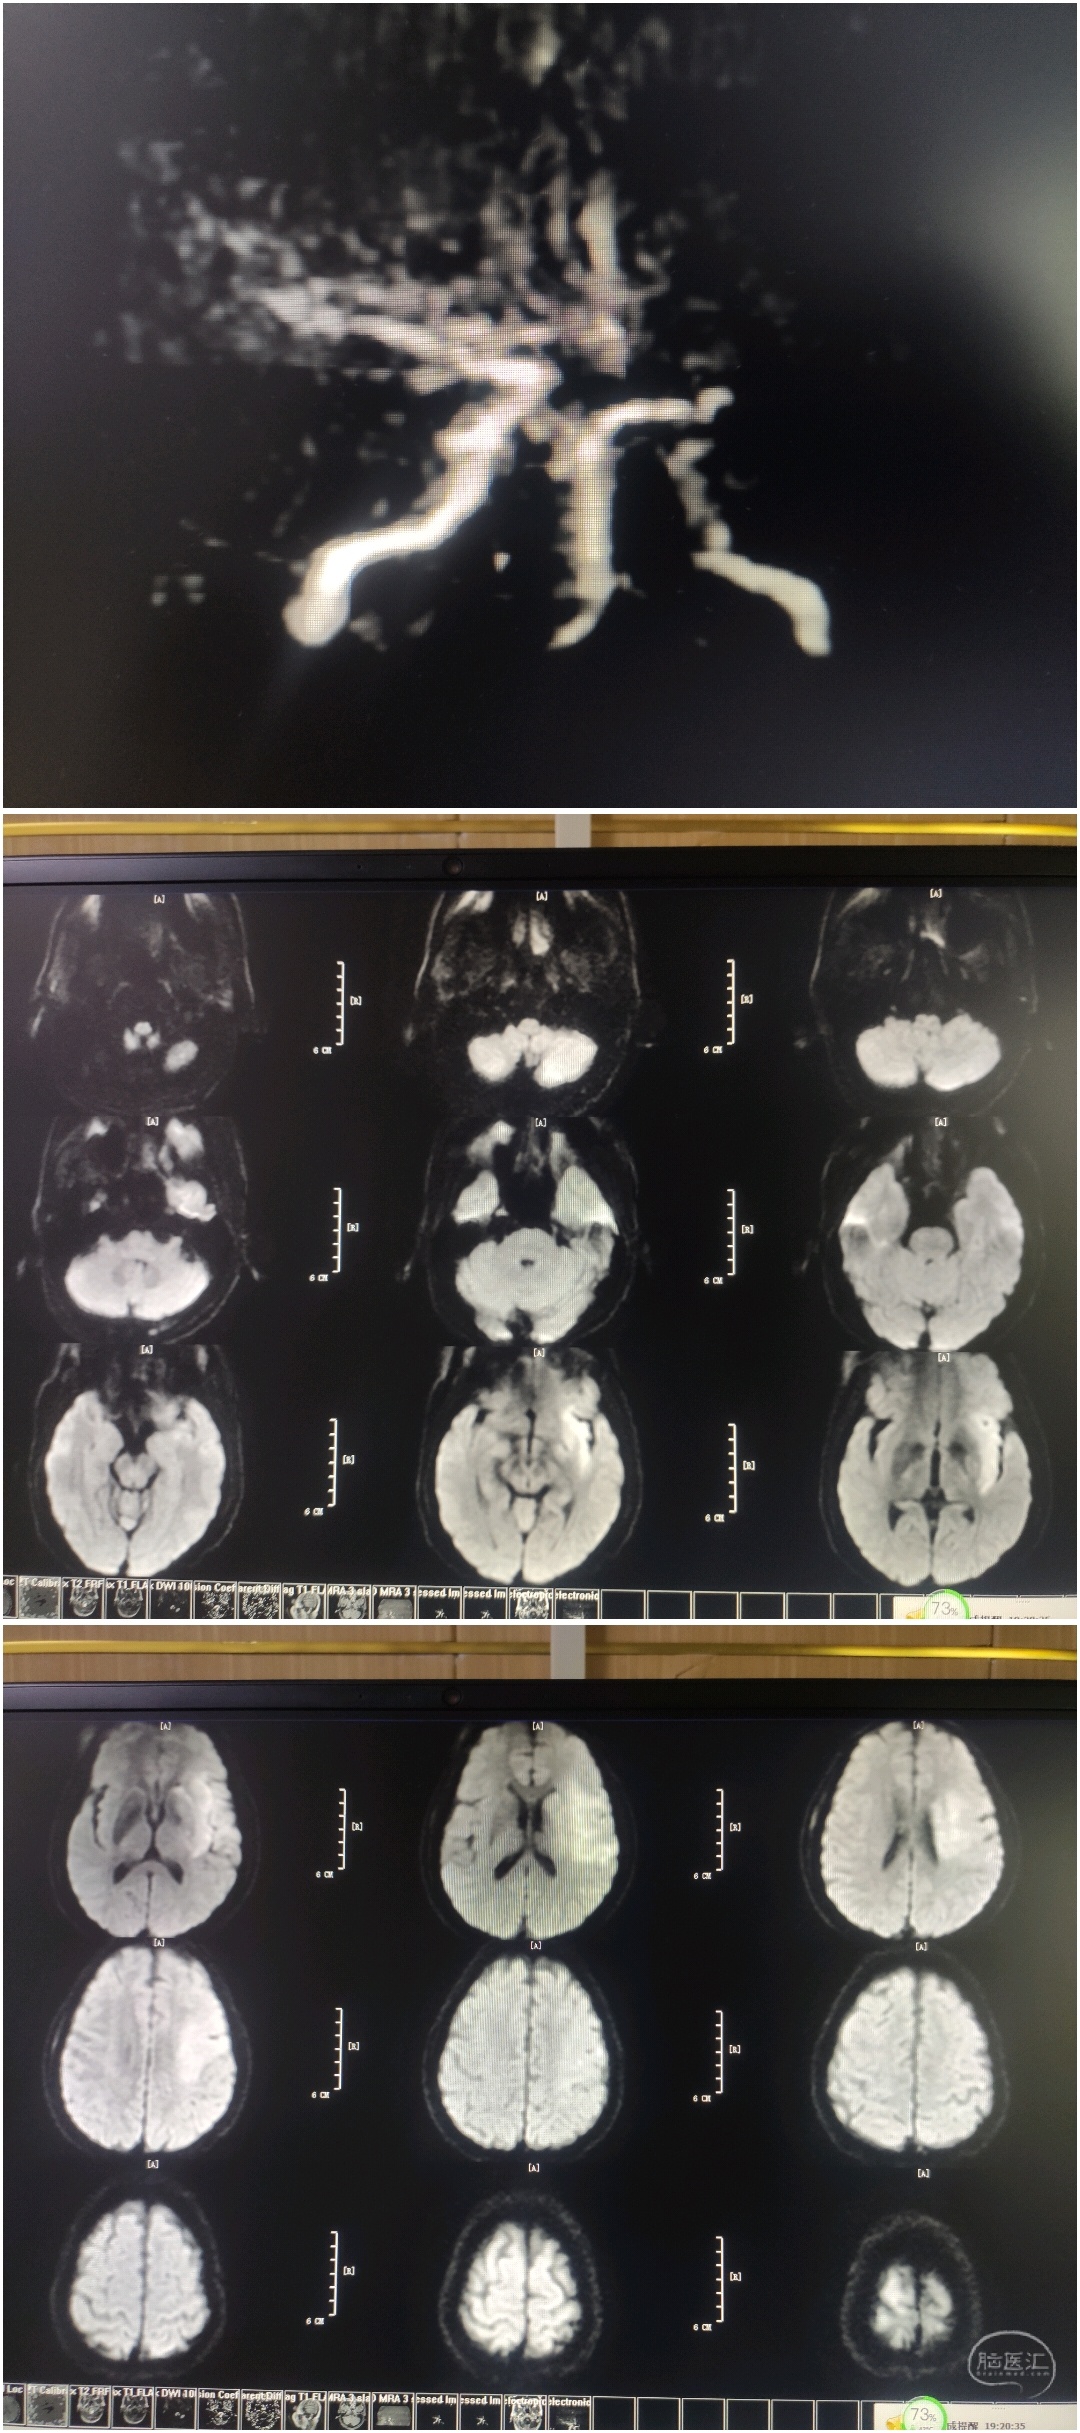

MRA提示:左侧颈内动脉末端及左侧大脑中动脉未见显影。DWI提示左侧大脑中动脉供血区高信号。DWI-Aspect评分:4分。醒后卒中,DWI信号不高,考虑存在大体积缺血半暗带,急诊血管内治疗。

65岁男性,主诉:发现右侧肢体无力,言语不能3小时。NHISS评分:16分,CT-ASPECT评分:5分。